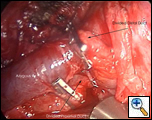

Exploration of this area bluntly will reveal the thoracic duct as a thin tubular structure with occasional peristalsis (Video 5). Once a sufficient length of duct is isolated it is doubly clipped using 5 or 10mm clips depending on the size of the duct and is divided (Figures 4-6). Transection with a linear cutting stapler with a vascular load (30mm length, 2.0mm staple height) works just as well (Video 6). The stapler or clip applier can be introduced through the working incision or the incision used for retraction of the diaphragm. If an adequate length of the duct can be isolated, a portion can be excised and sent for frozen section to confirm its identity.

| Figure 4: Thoracic Duct isolation. | Figure 5: Thoracic Duct Ligation. | Figure 6: Thoracic Duct Divided. |